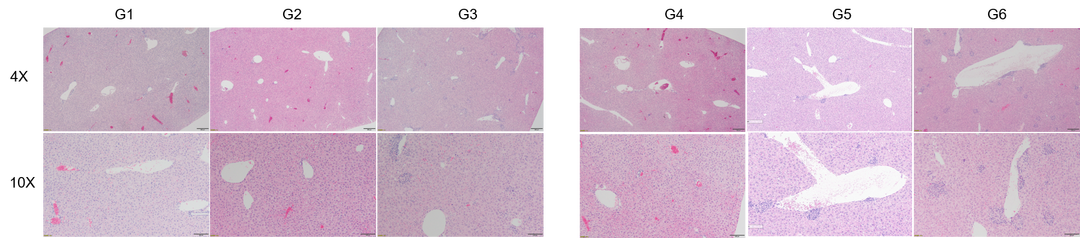

高剂量Urelumab 治疗可导致B-h4-1BB小鼠和B-h4-1BB/h4-1BBL小鼠肝脏淋巴细胞浸润增加

肝毒性的病理分析。在B-h4-1BB小鼠(G1-G3)中,当urelumab剂量为1mg/kg时,肝脏未见明显异常变化(G2)。当剂量为20 mg/kg (G3)时,观察到血管周围细胞浸润或肝脏慢性炎症,并伴有轻度病变。

在B-h4-1BB/h4-1BBL小鼠(G4-G6)中,1 mg/kg组(G5) 3/5的小鼠出现病理变化(轻度2/5,轻度1/5),而在20 mg/kg剂量(G6)时,所有实验动物肝脏均出现中度变化。总体而言,20 mg/kg组(G6)肝脏病变程度和发生率显著高于1 mg/kg组(G5)。

以上结果提示,高剂量(20mg /kg)的urelumab比低剂量(1mg /kg)的urelumab更容易发生血管周围细胞浸润或肝脏慢性炎症。B-h4-1BB/h4-1BBL小鼠对urelumab毒性作用比B-h4-1BB小鼠更敏感。因此B-h4-1BB/h4-1BBL小鼠是较好的临床前毒性评价模型。